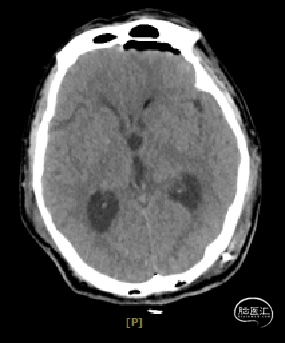

术后1天复查CT

术区无出血,脑室系统较术前显著缩小,脑积水缓解。